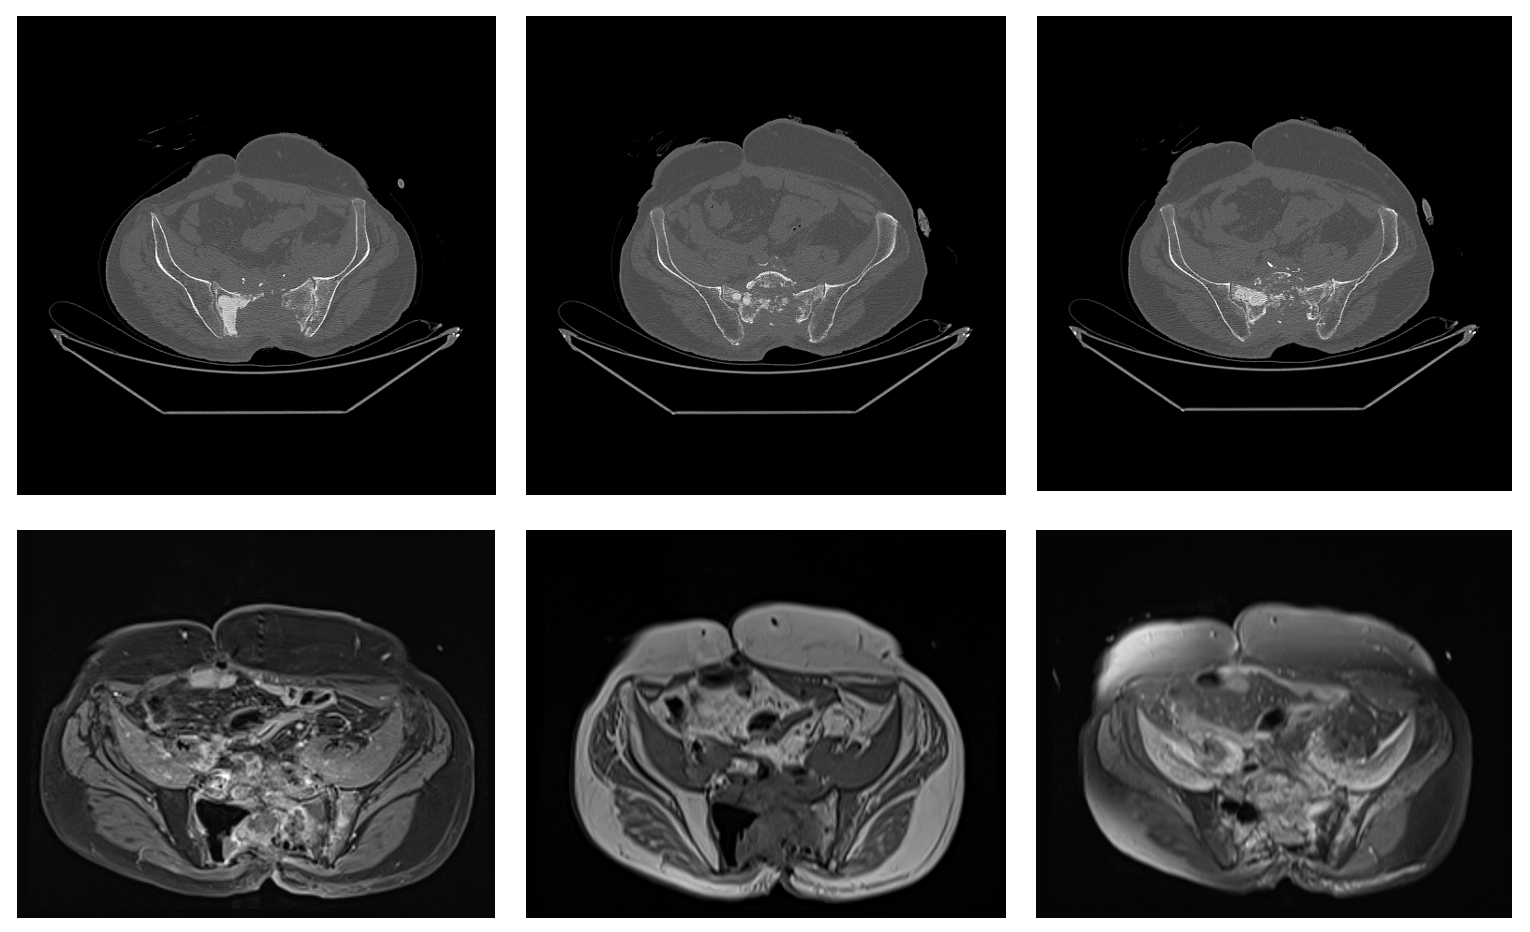

Ameliyat Öncesi: Tomografi ve MR’da sakrumda daha önce uygulanmış kemik çimentosu, harabiyet ve nüks tümör görülmekte.